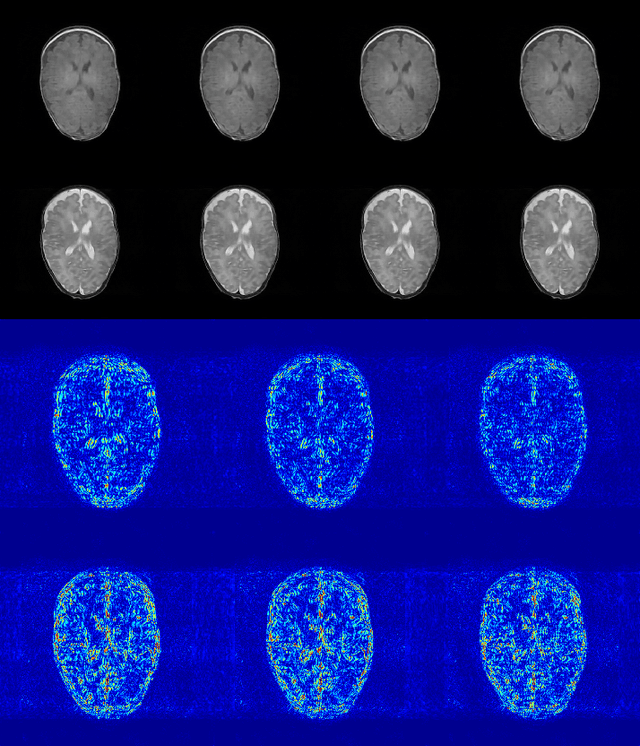

Abstract:In multi-contrast magnetic resonance imaging (MRI), compressed sensing theory can accelerate imaging by sampling fewer measurements within each contrast. The conventional optimization-based models suffer several limitations: strict assumption of shared sparse support, time-consuming optimization and "shallow" models with difficulties in encoding the rich patterns hiding in massive MRI data. In this paper, we propose the first deep learning model for multi-contrast MRI reconstruction. We achieve information sharing through feature sharing units, which significantly reduces the number of parameters. The feature sharing unit is combined with a data fidelity unit to comprise an inference block. These inference blocks are cascaded with dense connections, which allows for information transmission across different depths of the network efficiently. Our extensive experiments on various multi-contrast MRI datasets show that proposed model outperforms both state-of-the-art single-contrast and multi-contrast MRI methods in accuracy and efficiency. We show the improved reconstruction quality can bring great benefits for the later medical image analysis stage. Furthermore, the robustness of the proposed model to the non-registration environment shows its potential in real MRI applications.